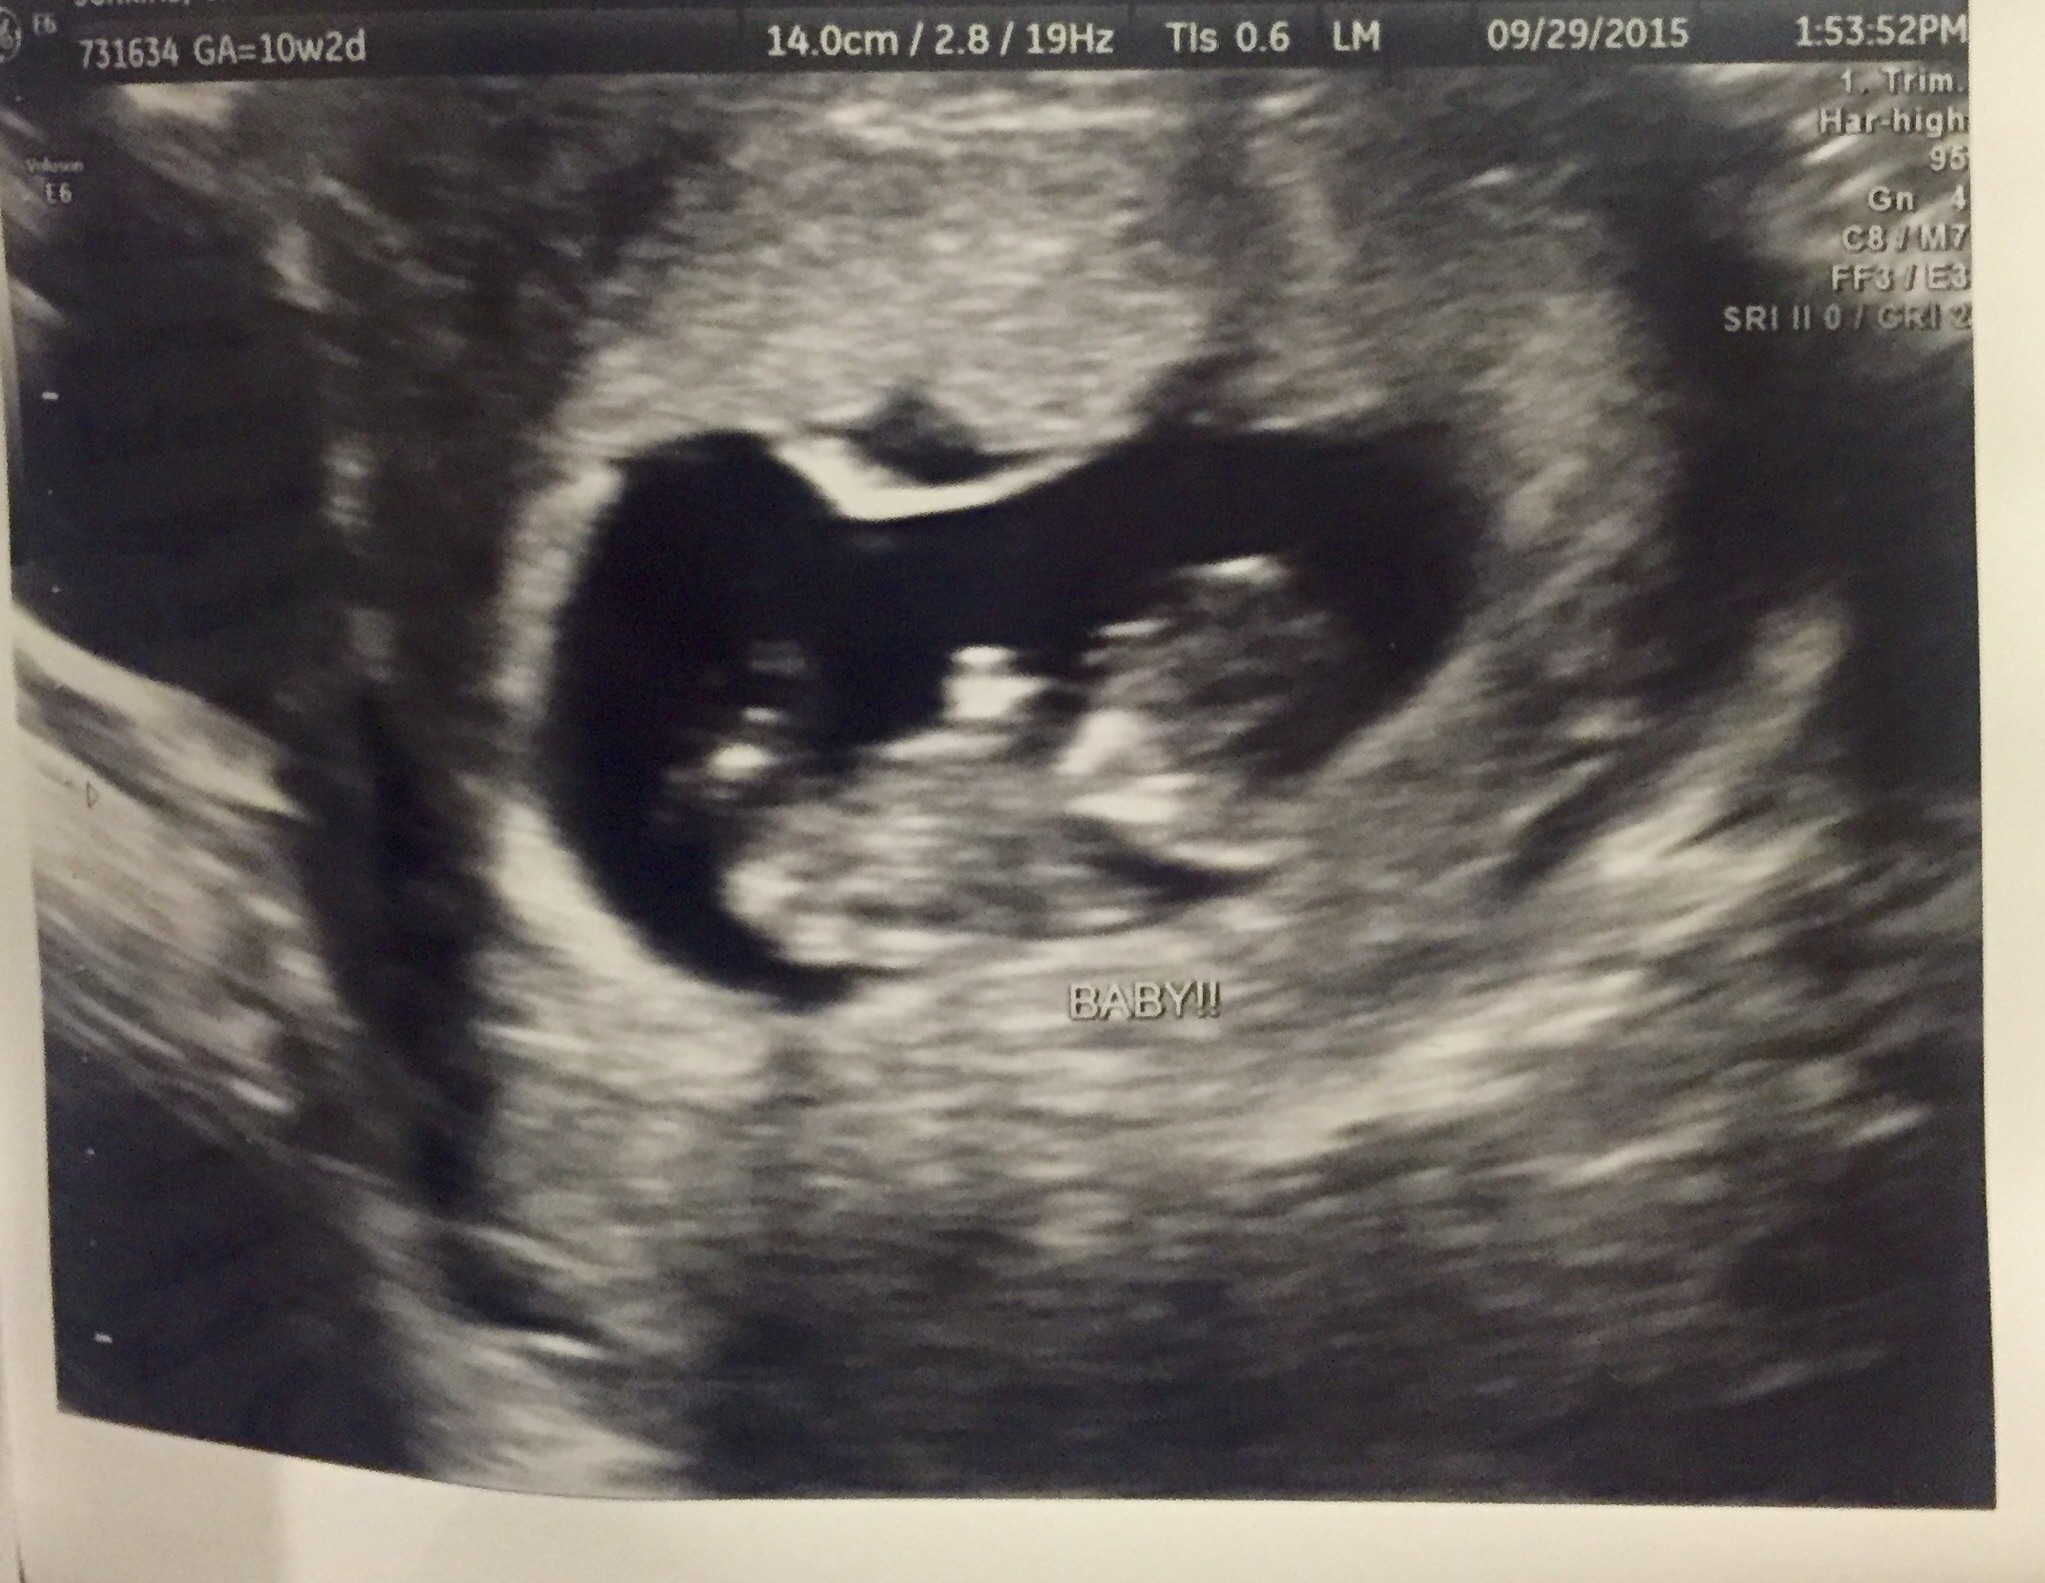

We had a 2nd yesterday at 10w4d (midwife was super kind to "gift" it to us when my and DH couldn't make out the heartbeat- she could hear it but we couldn't distinguish is from other sounds). We have a jumping bean! LO was doing kicks and flips and moving around like mad- it was so cute!!!

I've been impatiently waiting to share on this thread for the last several weeks - finally! 10w2d, FHR 169, it was so relieving. I think it looks like a little gummy bear- facing the camera and waving.